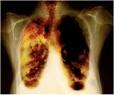

Así se quedan los pulmones de los fumadores, eso si un cáncer no se te lleva antes...